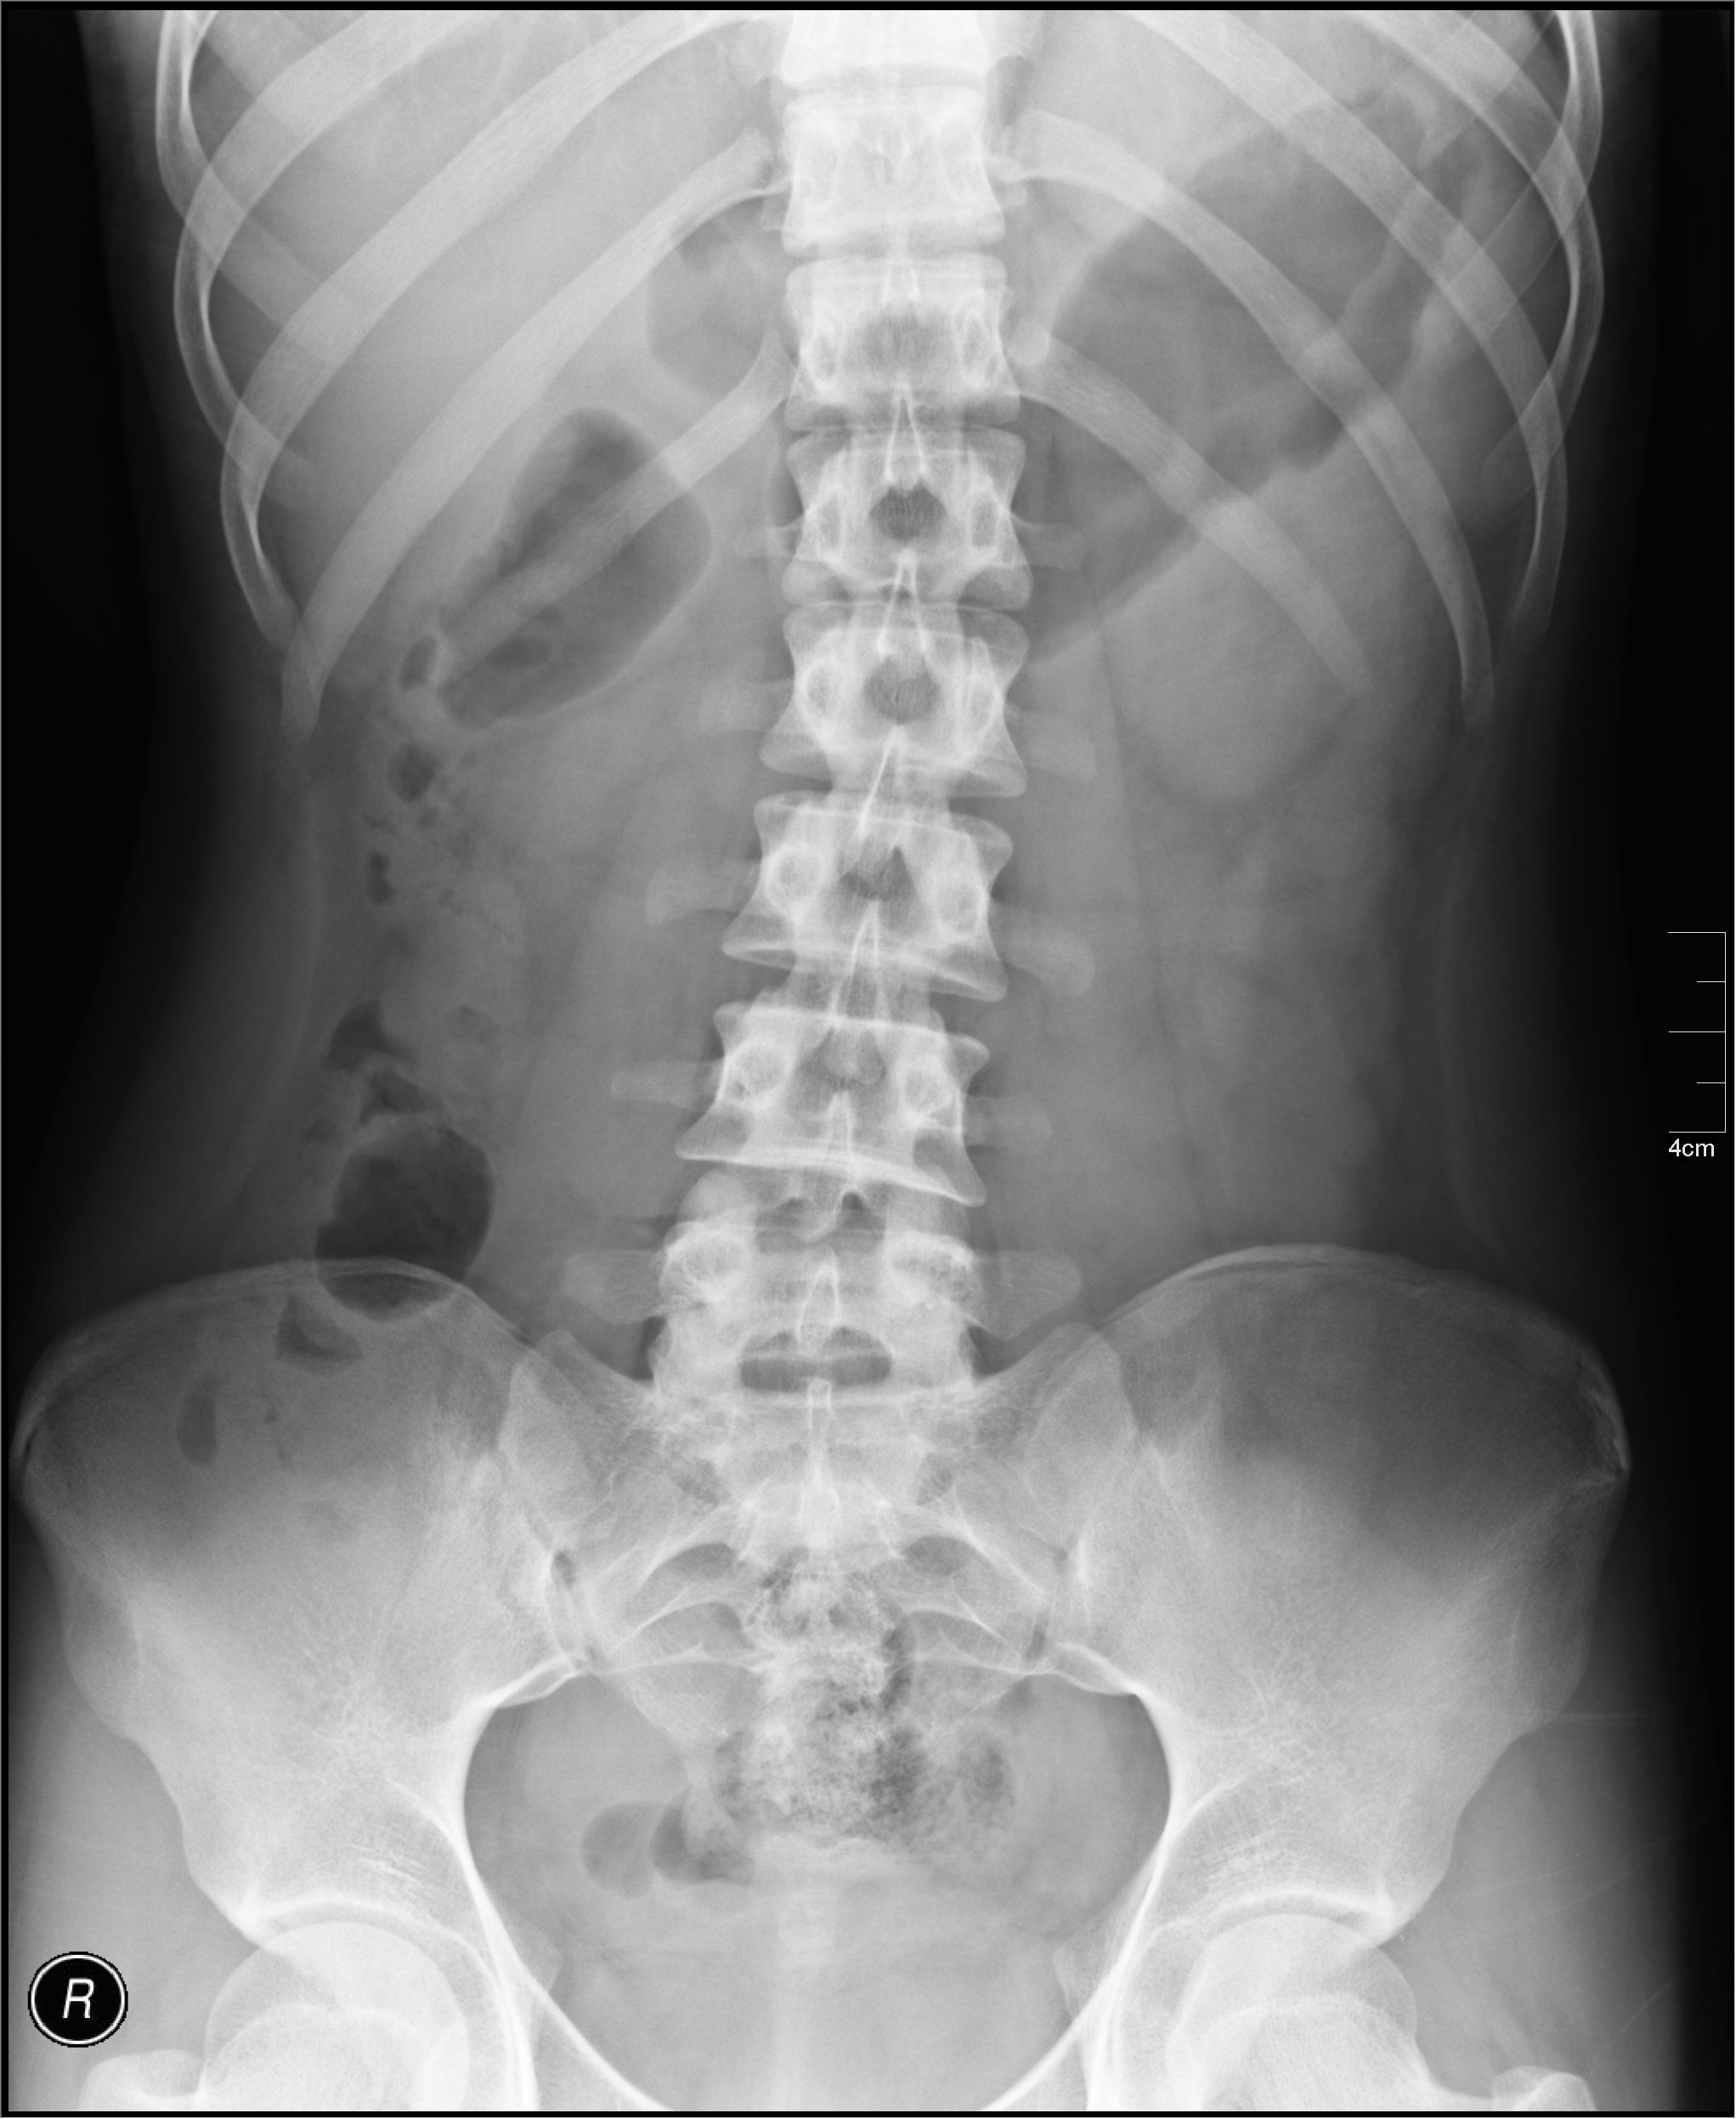

복부 엑스레이는 대장을 시각화하는 데 사용될 수 있다.

대장 질환은 혈변, 변비, 복통이나 발열을 유발할 수 있다. 대장 기능을 검사하는 검사에는 바륨 섭취 검사, 복부 X선 사진, 대장내시경이 있다.[18]

대장에 영향을 미치는 질병은 대장 전체 또는 일부에 영향을 미칠 수 있다. 충수염충수의 염증으로 인해 발생하는 대장의 질병 중 하나이다. 대장의 전신 염증을 대장염이라고 하며, ''클로스트리디움 디피실리균''에 의해 발생하는 경우 위막성 대장염이라고 한다.[18] 대장에 영향을 미치는 질병으로 인해 대변과 함께 혈액이 나올 수 있고, 변비가 발생할 수 있으며, 복통이나 열이 발생할 수 있다. 대장의 기능을 구체적으로 검사하는 검사에는 바륨 삼키기, 복부 엑스레이 및 대장 내시경 검사가 있다.[18]